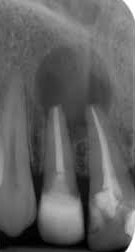

Periapikális/korona röntgen

Kisméretű röntgenfelvétel (kis fogröntgen), melyen egy kb. 2x3cm-es területet vizsgálhatunk. A kis dimenzió miatt a felvételek nagyon pontosak, torzításmentesek, kiválóan alkalmasak fogszuvasodás detektálására (korona röntgen), vagy foggyökér körüli kóros folyamatok diagnosztizálásra (periapikális röntgen). A fogszabályozásban a periapikális röntgeneket használjuk a miniimplantátumok helyzetének vizsgálatára, a behelyezés előtt és után. Sugárterhelése kisebb a háttérsugárzástól, mely minden nap ér minket.